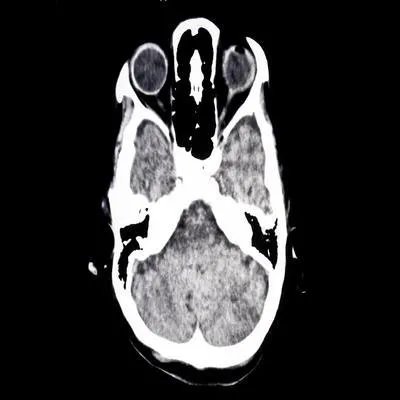

1、脑垂体瘤脑垂体瘤占颅脑肿瘤的10%左右。这是出现在腺垂体部位的一种阳性肿瘤。根据其分泌激素的不同又分为生长激素腺瘤、泌乳素腺瘤、肾上腺皮质激素腺瘤等等;此外还包括无分泌功能的腺瘤。2、脑膜瘤脑膜瘤占颅脑肿瘤的20%左右,它是来源于脑膜组织的一种肿瘤疾病,通常发生在大脑半球中线的附近,也有可能会发生在颅底部位。这种肿瘤大多数都是良性的,生长比较缓慢,而且一般是可以通过手术完全切除掉的。3、脑神经胶质瘤脑神经胶质瘤主要来源于神经胶质细胞。这种肿瘤包括星形细胞瘤、胶质母细胞瘤、髓母细胞瘤、少枝胶质细胞瘤等,此类肿瘤占颅脑肿瘤的40%左右。4、血管网状细胞瘤血管网状细胞瘤通常是发生在小脑部位的,也有少部分患者会出现在脑干及大脑等部位。此肿瘤是由血管组织所构成的,外观看起来是紫红色的。并且肿瘤的血供是非常丰富,不过边界是比较清晰的,通过手术有完全切除的可能。颅脑肿瘤的分类就先介绍这些,颅脑疾病对身体的危害性是比较大的,所以不管出现的是哪种颅脑肿瘤,都应该尽快到专业医院诊断及处理。日常生活当中要注意休息,减少剧烈活动,避免让颅内压增高。同时还要少吃刺激、油腻的食物,尽量以清淡营养的为主。